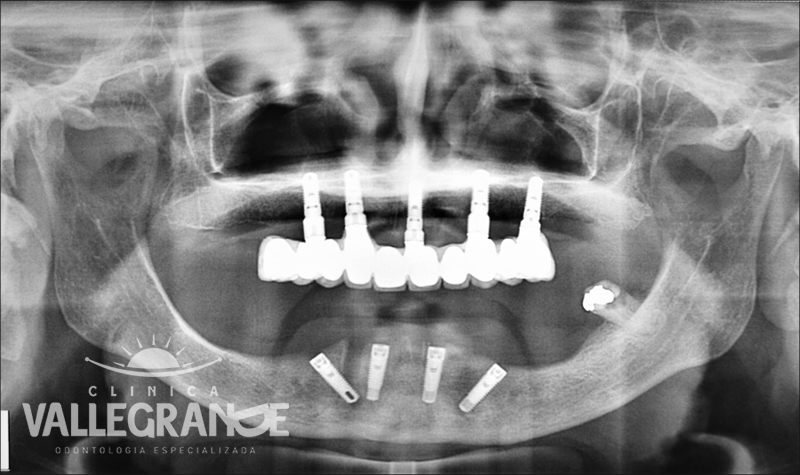

Caso planificado con prótesis híbrida fija completa sobre 4 implantes mandibulares.